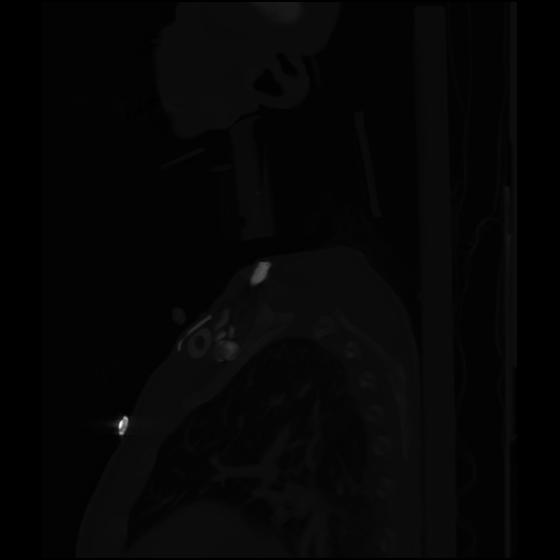

24 ANGIO,CE,Sag-MIP,5.000,ANGIO,Sag-MIP,